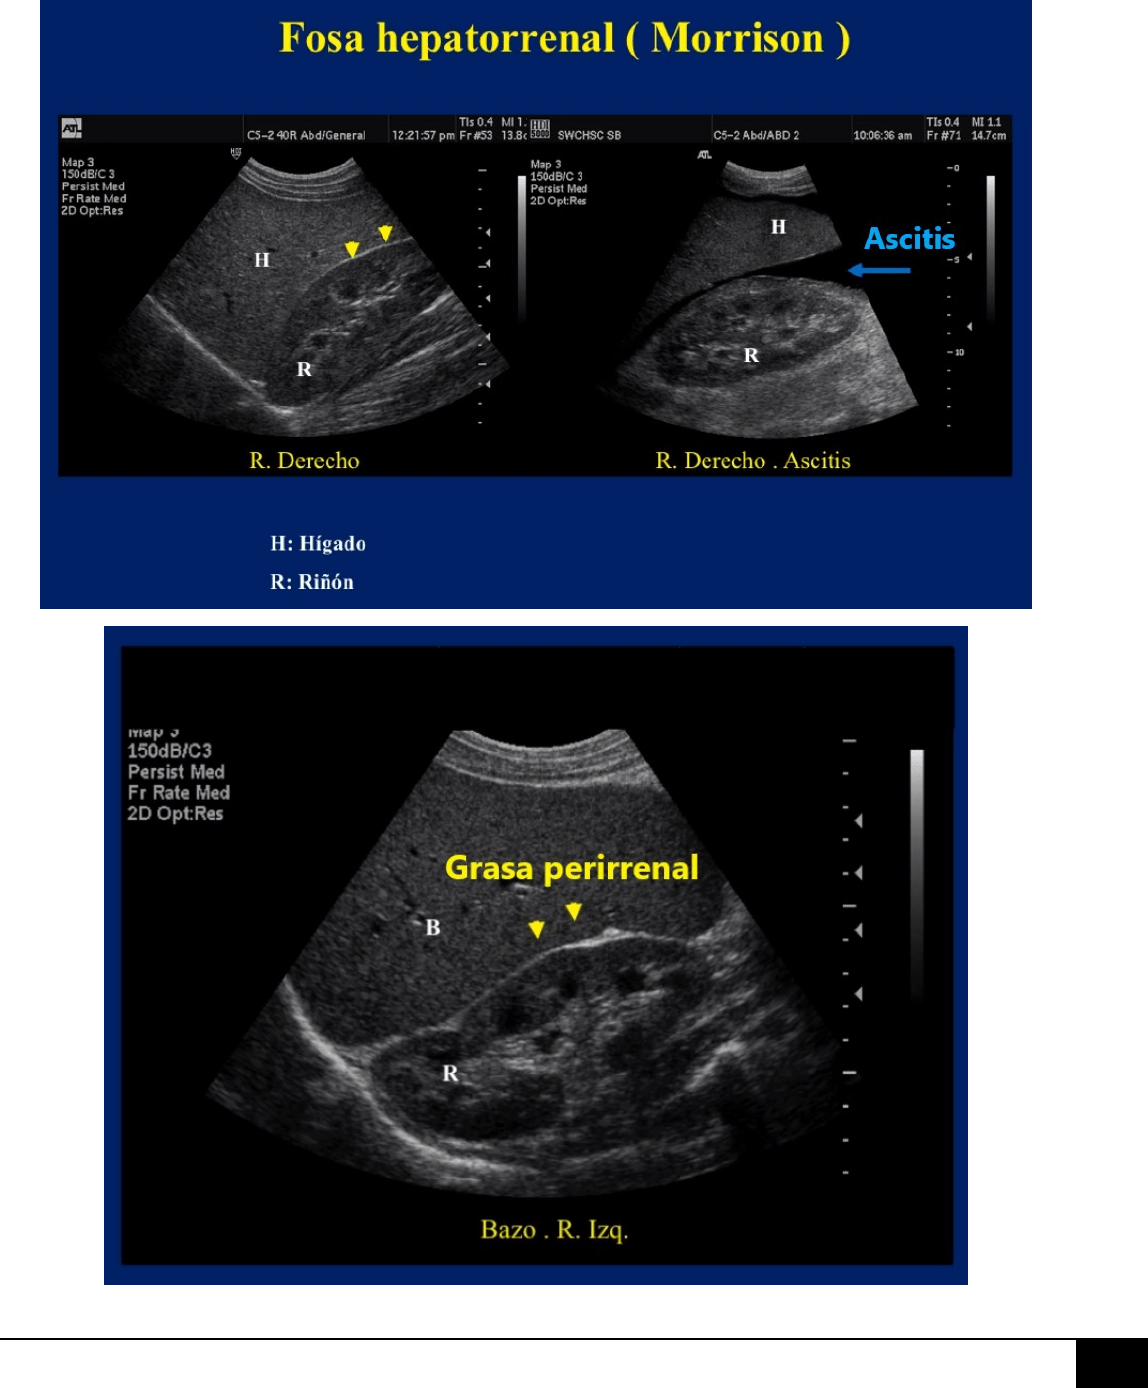

POSTERIOR o “FOSA DE MORRISON”:

Espacio más declive del abdomen en el

paciente en decúbito supino y, por

tanto, un sitio frecuente de acúmulo de

líquido, hemoperitoneo, metástasis y

abscesos. Está separado del espacio

subfrénico derecho por el LTD, pero

ambos espacios comunican libremente

entre sí alrededor del borde del LTD.